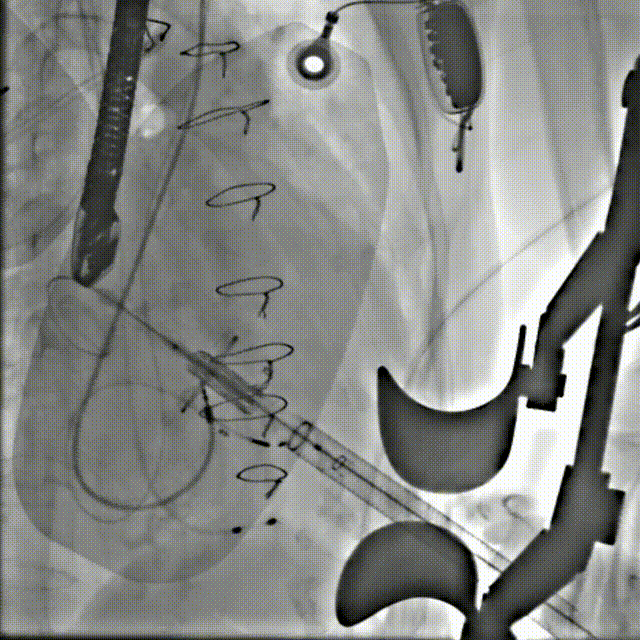

术中影像

球扩释放

释放后

6atm球扩释放,植入Renatus 23#,瓣架形态良好,位置理想。